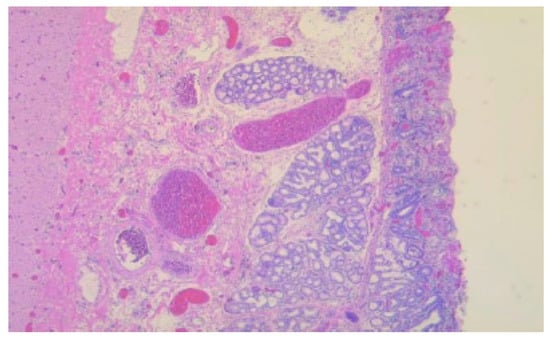

According to the Heinrich classification, modified by Gaspar-Fuentes et al., there are four histological types of EPT: type I—presenting acini, ducts, and islets (complete heterotopia), type II—presenting only ducts (canalicular heterotopia), type III—presenting only acini (exocrine heterotopia), and type IV—presenting only islets (endocrine heterotopia) [19]. 5 out of the 6 cases evaluated belonged to type I and 1 case belonged to type III (Figure 1, Figure 2, Figure 3 and Figure 4).

Figure 4. Duodenal wall with erosions and regenerative epithelium in the adjacent sections with ectopic pancreas, HE, 50×.